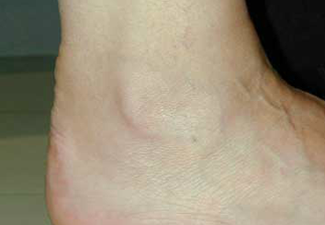

Tendinitis no insercional:

Peritendinitis del aquiles. Observese la inflamación en la cara posterior.

Notese ensanchamiento del tendón de aquiles.